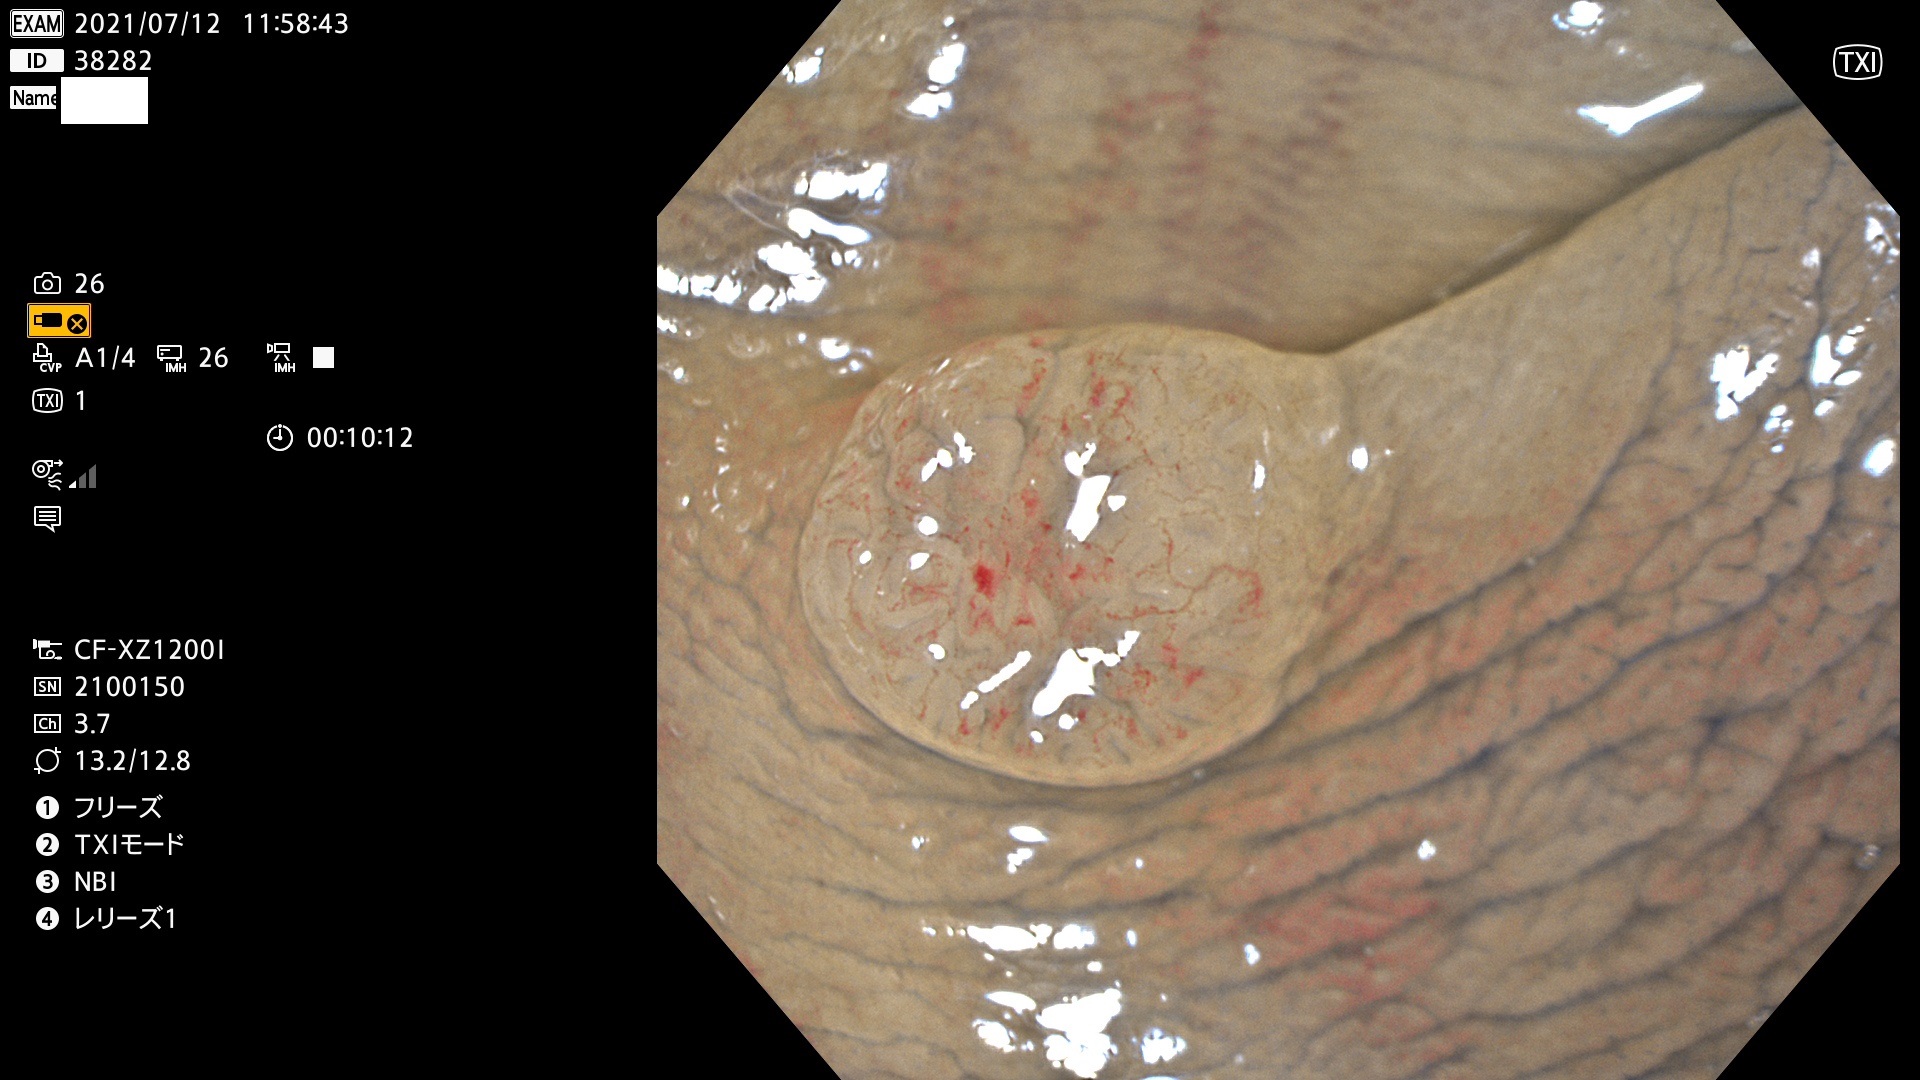

38200 38201 38202 38203 38204 38208 38209 38210 38211 38212 38213 38214 38215 38219 38220(SSAPのみ) 38221 38225 38226 38227 38228 38229 38230 38231 38232(SSAPのみ) 38233 38234 38235 38237 38238 38239 38240 38241 38242 38244 38245 38246 38247 38248 38249 38250 38251 38252 38253 38254 38256 38257 38258 38259 38260(SSAPのみ) 38262 38265 38267 38268(SSAPのみ) 38269 38270 38272 38273 38274 38276 38278 38280 38281 38282 38283 38284 38287 38288 38289 38290 38291 38292 38295 38296 38297 38298 38299(SSAPのみ)

発見困難で危険性の高い平坦型病変(上記100名より抽出)